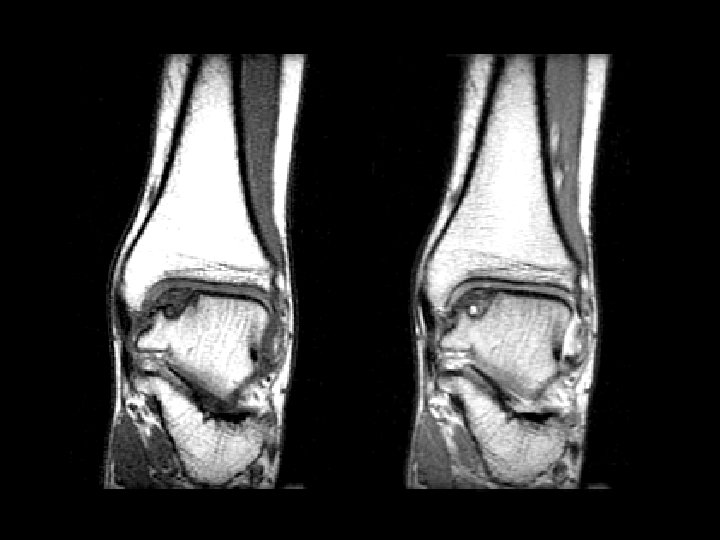

Bucket-Handle Tear • • Findings: – “double PCL sign” - torn meniscus BELOW normal PCL on sag view – Above ACL on cor view – Truncation of medial meniscus – Joint effusion Medial = 3 x lateral Locked knee ddx: – torn ACL, PCL – torn meniscus